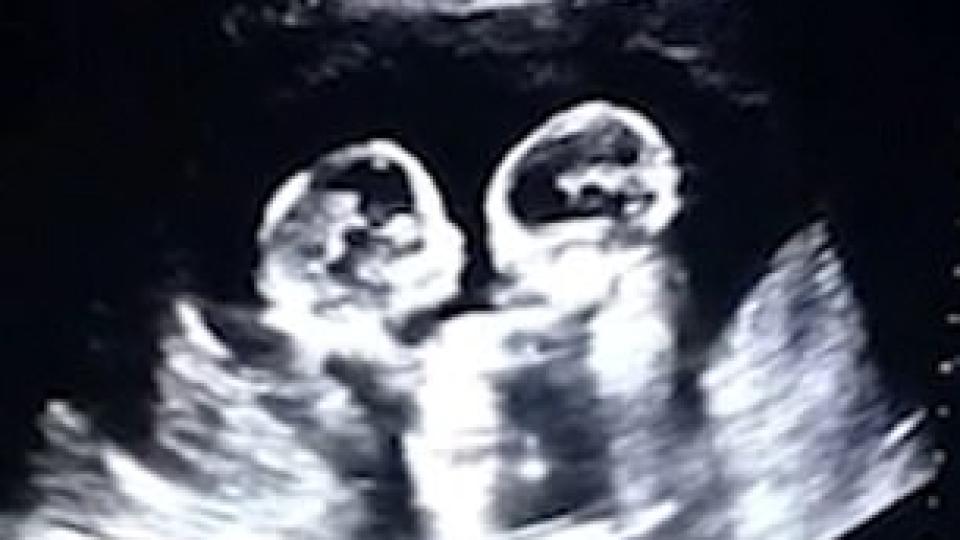

На тези родители от Китай със сигурност ще им е много трудно да гледат близначките си, защото те са започнали да се бият още в утробата на майка си. Видео, запечатало спречкването народените момиченца, се превърна в истинска сензация в мрежата. По време на поредния ултразвук в 4-ия месец от бременността на майката, бъдещият татко е заснел с камерата си много забавна сцена. Той е успял да улови как момиченцата се "боксират" в корема на съпругата му.

28-годишният татко споделя, че не е очаквал момичетата му да станат популярни още преди да са се родили. И добавя, че това не е единственият случай, в който момичетата са се сборичкали в корема на майка си. Но и не винаги са се карали.

На един от прегледите с видеозон той и жена му видели как двете момиченца се прегръщат.

Щастливите родители добавят, че дъщерите им са идентични близначки, делящи една и съща амниотична торбичка в матката. Такива моноамниотични близнаци са изключителна рядкост.

Подобна бременност се среща веднъж на 60 000 случая.

Палавите момичета се раждат на 8 април и са напълно здрави. Малките дами си имат и прякори - Череша и Ягода - любимите плодове на майка им.

Забавното видео вижда бял свят едва след раждането на момиченцата. За отрицателно време то се превърна в истински вирус и е гледано над 2,5 млн. пъти. А коментарите под него не спират да валят.